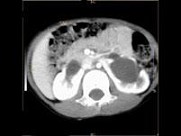

- 多项选择题女,6个月, CT扫描如图所示,下列说法正确的是 ( )

A、双侧肾盂积水

B、双侧肾门朝向前内方

C、双肾下极融合

D、考虑为异位肾

E、考虑为马蹄肾

- 女,6个月, CT扫描如图所示,下列说法